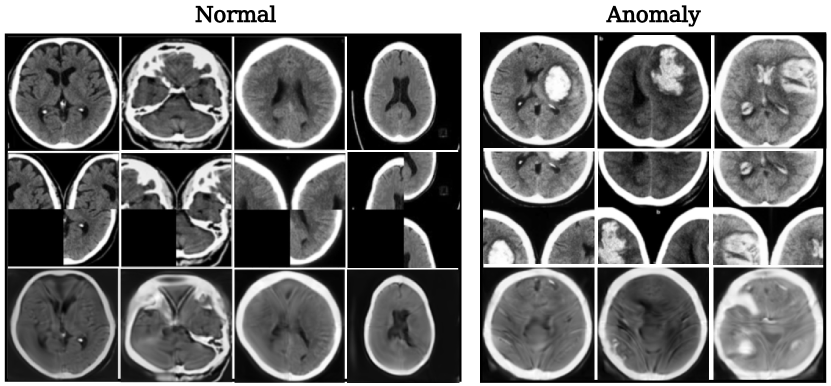

Datasets. We considered seven datasets for evaluating our method: MNIST, Fashion-MNIST, CIFAR-10, COIL-100, MVTecAD, and two medical datasets (Head CT (hemorrhage) and Brain MRI Images for Brain Tumor Detection). We briefly describe each of these datasets:

MNIST [41]: 60k training and 10k test 28×28282828\times 28 gray-scale handwritten digit images from 0 to 9. Fashion-MNIST [44]: 60k training and 10k test grayscale images of 10 fashion product categories. CIFAR-10 [12]: 50k training and 10k test 32×32323232\times 32 color images in 10 classes. COIL-100 [48]: 7200 128×128128128128\times 128 color images of 100 object classes with 72 images of each object in different poses. MVTecAD [18]: an industrial dataset with more than 5k high-resolution images in 15 categories of objects and textures. Each category contains both normal and anomalous images with various kinds of defects (used for testing). We downscale all images to the size 128×128128128128\times 128 and use zoom data augmentation to create 800 training images for each class. Head CT (hemorrhage) [19]: a medical dataset containing 100 128×128128128128\times 128 normal head CT images and 100 with hemorrhage. Brain MRI Images for Brain Tumor Detection [20]: a medical dataset with 98 256×256256256256\times 256 normal MRI images and 155 with brain tumors.